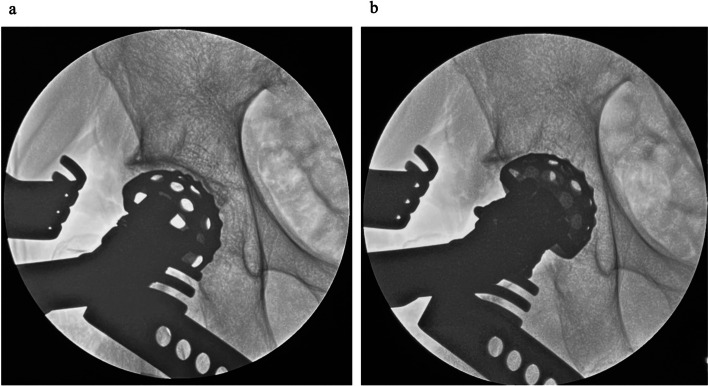

Methods: This retrospective study included 101 patients who received primary THA via the direct anterior approach using a conventional traction table with fluoroscopy between July 2022 and October 2024. Two observers evaluated radiological outcomes using postoperative anteroposterior X-rays. The intraclass correlation coefficients of cup positioning angles were calculated (inclination: 0.92, anteversion: 0.89 for intra-observer agreement; inclination: 0.91, anteversion: 0.85 for inter-observer agreement). Complications were defined as dislocation, periprosthetic fracture, ankle fracture, implant loosening, nerve injury, surgical site infection, deep vein thrombosis, and revision surgery for any reason.